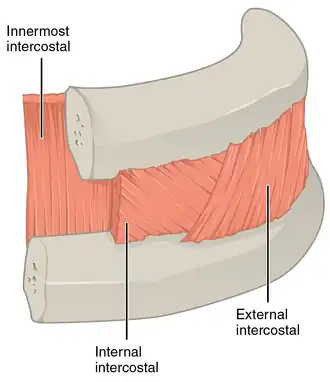

The muscles extend from the tubercles of the ribs behind, to the cartilages of the ribs in front, where they end in thin membranes, the external intercostal membranes, which are continued forward to the sternum. These muscles work in unison when inhalation occurs. The internal intercostal muscles relax while the external muscles contract causing the expansion of the chest cavity and an influx of air into the lungs.

Each arises from the lower border of a rib, and is inserted into the upper border of the rib below. In the two lower spaces they extend to the ends of the cartilages, and in the upper two or three spaces they do not quite reach the ends of the ribs.

They are thicker than the internal intercostals, and their fibers are directed obliquely downward and laterally on the back of the thorax, and downward, forward, and medially on the front.